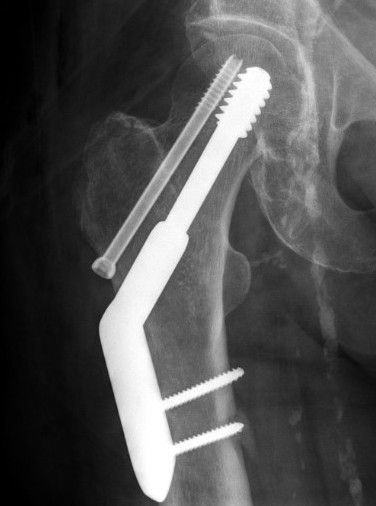

Sliding hip screw (SHS/DHS) + derotation screw

DHS and derotation screw

Youtube step by step sawbone guide